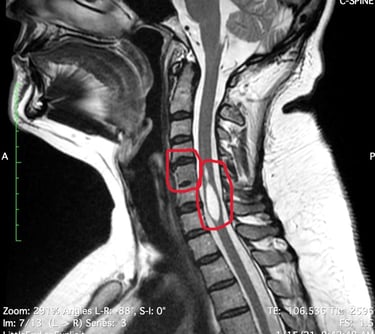

That MRI resulted on the finding of a syrinx, which is a cyst inside the spinal cord (Syringomyelia), full of cerebroespinal fluid (CSF) and obstructing the canal. The radiologist also found the fusion of two cervical vertebraes (Klippel-Feil) and led her to see a neurosurgeon who said he didn't have the experience to treat her but assured her symptoms were not related to this finding.

Her symptoms list continued to increase (weakness, numbness, dizziness, palpitations and irregular heart rate) and so the number of doctors she would see, trying to find answers, and that's when she decided to have a consultation with a doctor in the US (in July 2021) who confirmed three diagnoses: Syringomyelia, Klippel-Feil and Tethered Cord. This last anomaly was found on MRI images she had from 2019, which had been seen by several doctors (radiologists, orthopedist, neurosurgeon and family doctor) but none of them were able to see the defect.

KLIPPEL-FEIL SYNDROME

Is a rare disorder where two or more vertebrae in the neck are fused together from birth. People living with Klippel-Feil syndrome may have a short neck limited movement, and pain. It is estimated that this syndrome occurs in approximately 1 in 40,000 to 42,000 newborns worldwide.

MRI imaging is often used to evaluate people with symptoms of TSCS. Doctors can use MRI imaging to diagnose where the tethering is located, whether the base of a patient's spinal cord (the conus medullaris) is lower than normal, or if a tumor or a fatty mass (known as a lipoma) is causing the symptoms of TSCS.